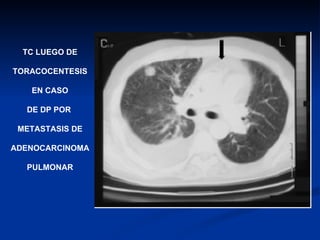

TC LUEGO DE TORACOCENTESIS EN CASO DE DP POR  METASTASIS DE ADENOCARCINOMA PULMONAR

TC LUEGO DETORACOCENTESIS EN CASO DE DP POR METASTASIS DE ADENOCARCINOMA PULMONAR